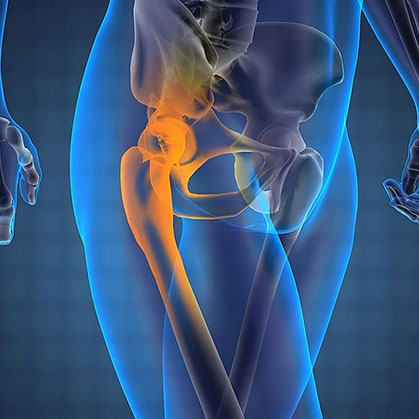

Боль в костях таза

Боль в костях таза возникает при травмах, воспалительных и невоспалительных заболеваниях, опухолях костей, мягкотканных структур, болезнях крови, нарушениях обмена в костной ткани. Может быть сильной, слабой, постоянной, периодической, острой, тупой, ноющей, колющей, тянущей, дергающей, пульсирующей. Иногда связана с физической нагрузкой, другими обстоятельствами. Причину боли выясняют с помощью опроса, внешнего осмотра, данных рентгенографии, УЗИ, других инструментальных и лабораторных исследований. До постановки диагноза рекомендован покой, иногда возможен прием анальгетиков.

Тазовая боль (Боль в тазобедренном суставе)

Боль в тазобедренном суставе, как правило, свидетельствует о появлении патологического процесса в анатомических структурах самого сустава либо прилегающих к нему тканей и органов. Наиболее часто болевые ощущения вызывает механическое повреждение, воспалительный процесс, инфекционное либо эндокринное заболевание. Не исключены и другие факторы, которые могут спровоцировать появление этого симптома. Рассмотрим, почему болит тазобедренный сустав и как справиться с этой проблемой.